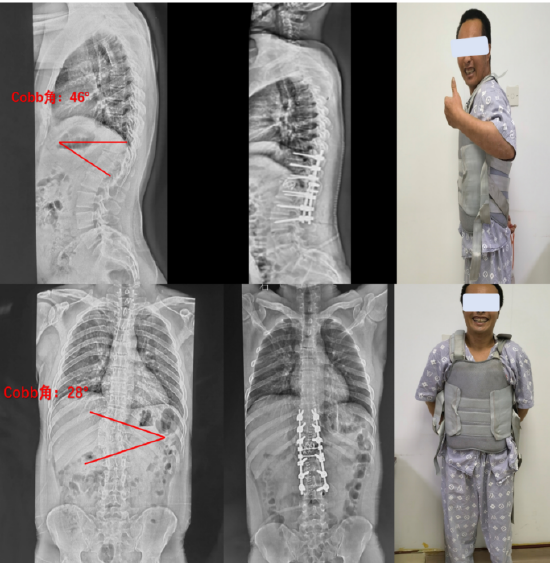

黎燕清,女,56岁,胸椎后凸畸形,t8,9椎体骨折,as并al,op,清远职工医保

病例分享胸腰段脊柱后凸畸形